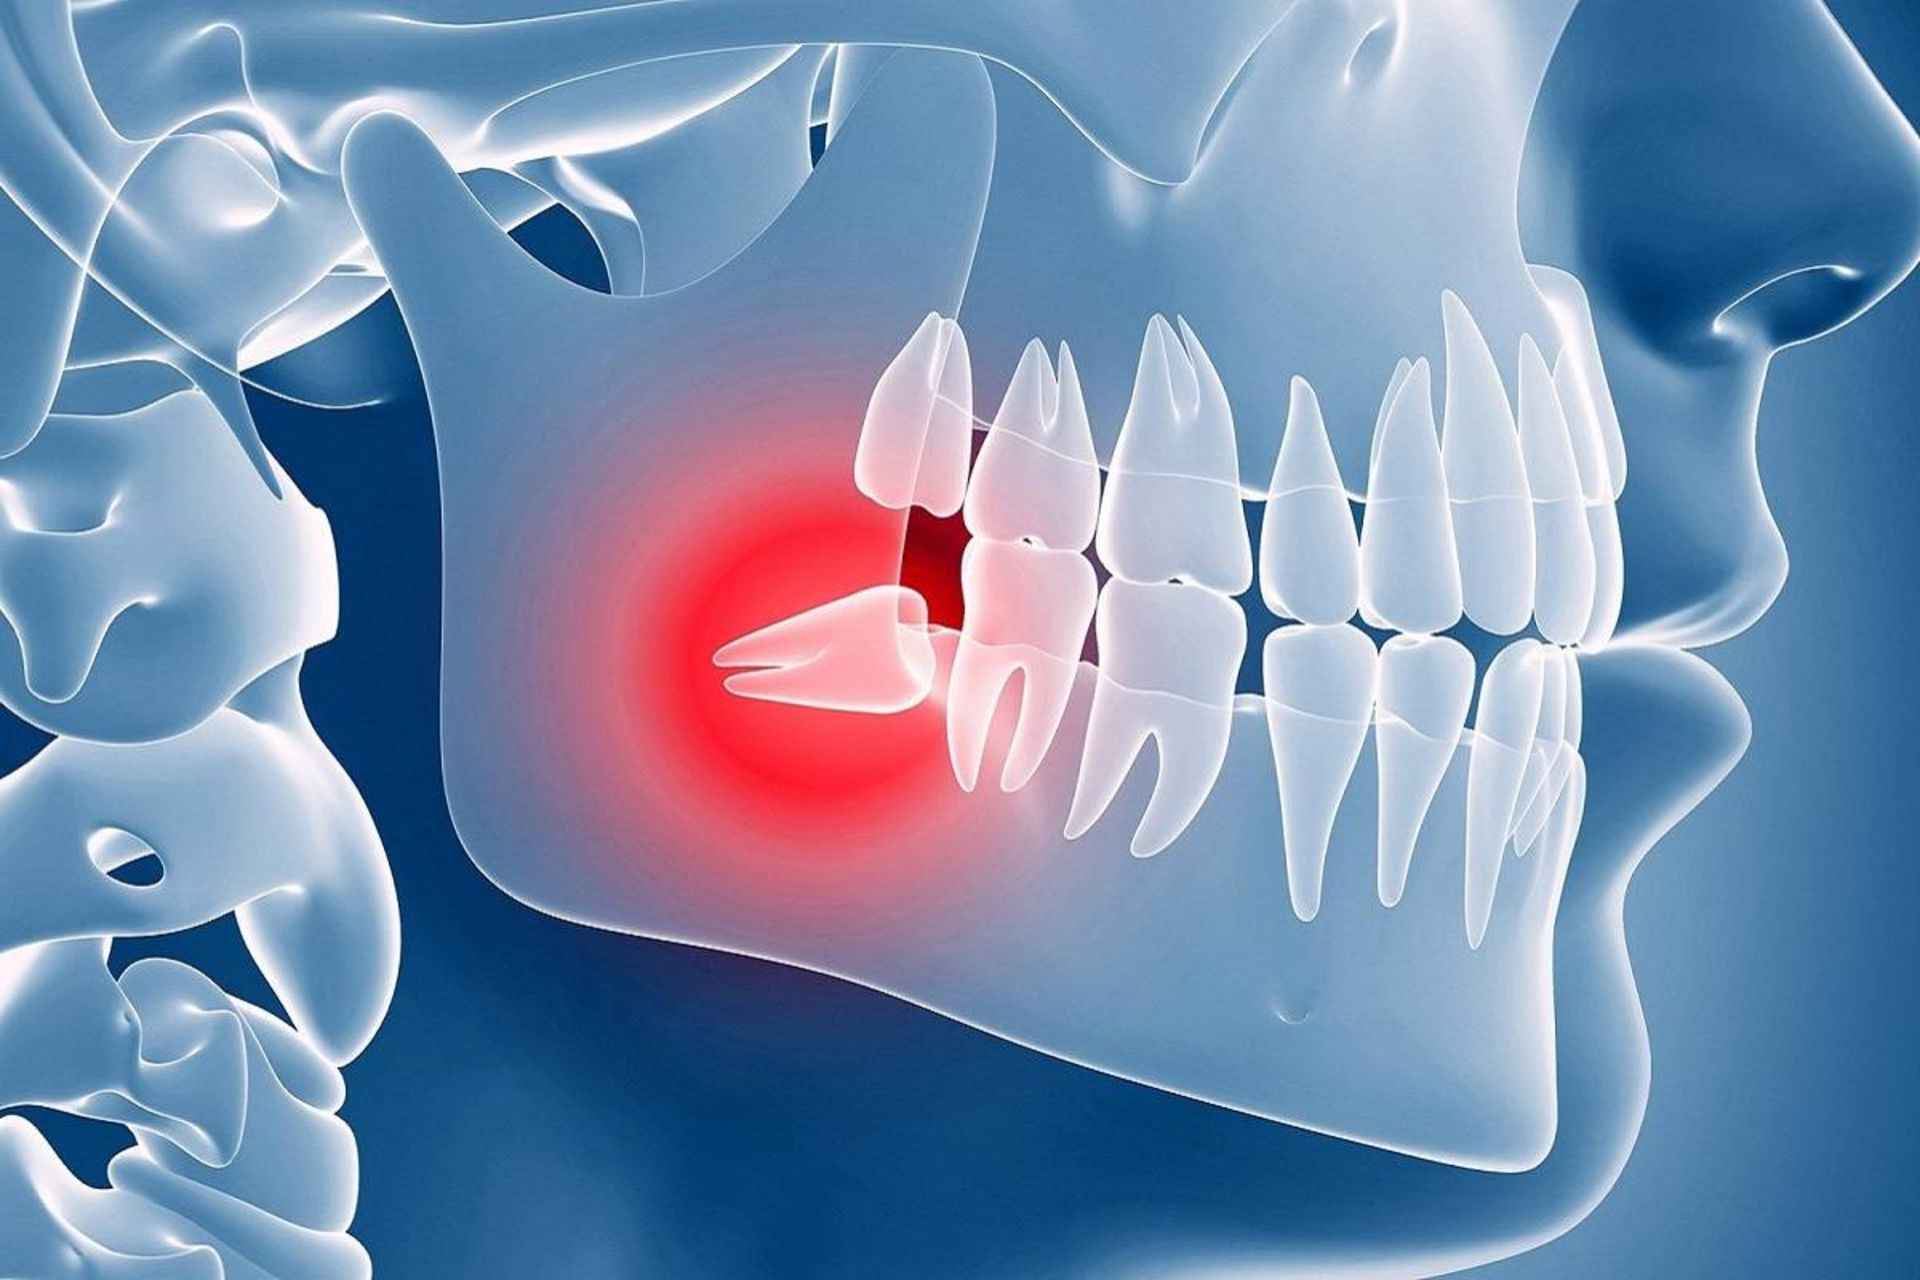

با‌این‌حال، فقط اینکه دردی از جانب دندان‌های عقل خود احساس نمی‌کنید، بدان معنا نیست که هیچ مشکلی وجود ندارد. این دندان‌ها ممکن است گیر افتاده یا نهفته باشند. این بدان معنا است که آن‌ها نمی‌توانند از فک خارج شوند و وارد دهان شوند. شاید دهان شما بسیار کوچک است و فضایی برای آن‌ها وجود ندارد یا این دندان‌ها به سمت دندان‌های دیگر در حال رشد باشند. آن‌ها می‌توانند به دندان مجاور فشار وارد کرده و به آن آسیب بزنند.

دندان نهفته. گاهی‌اوقات استخوان فک و دندان‌های دیگر مانع از بیرون آمدن دندان‌های عقل می‌شوند و این دندان‌ها زیر خط لثه گیر می‌کنند. این امر می‌تواند موجب درد شدیدی در دهان شود. دیگر علائم دندان عقل نهفته شامل درد در اطراف دندان‌های آسیاب بزرگ اما عدم نشانه‌ای از دندانی درحال بیرون آمدن باشد. ممکن است همچنین در قسمت پشت دهان شما کیست ایجاد شود.